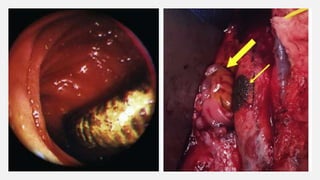

• #16 Figure 1 : Graft enteric fistula : A direct communication between the arterial circulation and the GI tract at the level of the suture line Figure 2 : Graft enteric erosion : Communication between the GI tract and the graft interstices